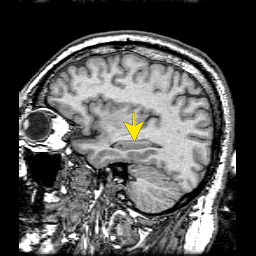

091hipposagi.png